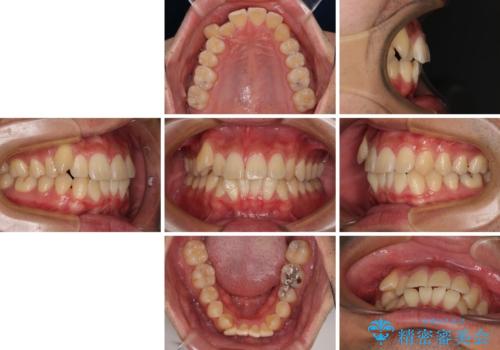

八重歯を無理なくなおしたい ワイヤー装置による非抜歯矯正治療

- 前歯のデコボコと右上の八重歯を気にして来院された患者様です。

マウスピース矯正とワイヤー矯正で悩んでいらっしゃいましたが、非常に強い咬合力であることや、お仕事柄不規則な生活リズムになることが多いとのことで、ワイヤー装置にて矯正治療を行うこととしました。

口元が突出する仕上がりとならないように、舌突出癖改善のトレーニングをしっかりと行っていただきながら、矯正治療を進めていくこととしました。

1年強でワイヤー装置を外すことができ、思ったよりも短期間で終了したため、患者様には大変喜んでいただきました。